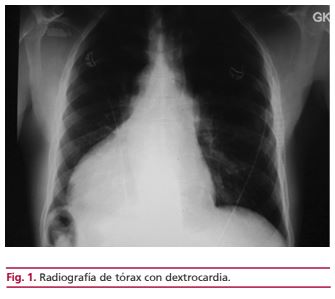

Situs inversus totalis asociado con origen anómalo coronario

IMÁGENES EN CARDIOLOGÍA